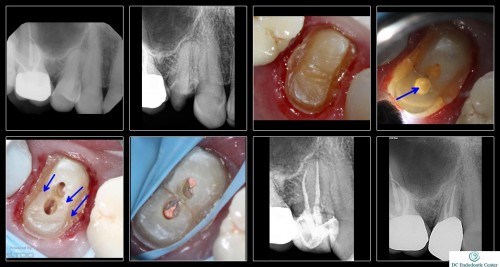

I wanted to post this interesting case. She is the sister of an endodontist colleague( no pressure) who arrived in my office with a temp crown and in severe pain. As soon as I took a look, I realized the tooth had a bad MD vertical fracture with no probings or mobility but would likely need extraction. I opened the tooth and decided to do a dual access to remove the least amount of tooth structure in the most vulnerable spot, right where the fracture was running. My thought was, I would loose nothing in pushing the envelope. She returned 4 weeks later and was completely asymptomatic and able to bite and chew so she really wanted to give it a try. After I completed the case (04/ 20 preps on both canals) the tooth was on and off acting up. With the GD, we finally agreed to extract it. The patient says after that appointment, the tooth never bothered her again. The final X-ray is an 18 month follow up. Tooth is completely asymptomatic and fully functional.

Cases like this prove how poor we are at prognosticating. We all recognize this tooth is probably history—but from the patient’s perspective, it seems to be working. AQnd as long as the patient understands we are just “buying her some time”, why not make the bet. I think all of us who have practiced for awhile have a very pessimistic view with this tooth. When, and if, the tooth comes out, we should ask the patient whether she feels it was worth the risk and expense. I think most patients would be appreciative of the effort.